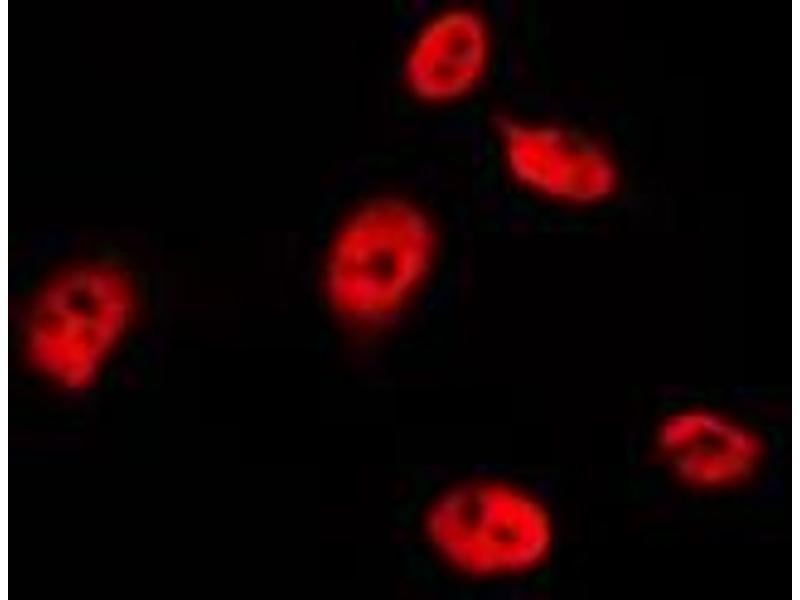

TP53 Reaktivität: Human WB, IF, IHC (p) Wirt: Kaninchen Polyclonal RB07990 unconjugated

Produktnummer ABIN390200